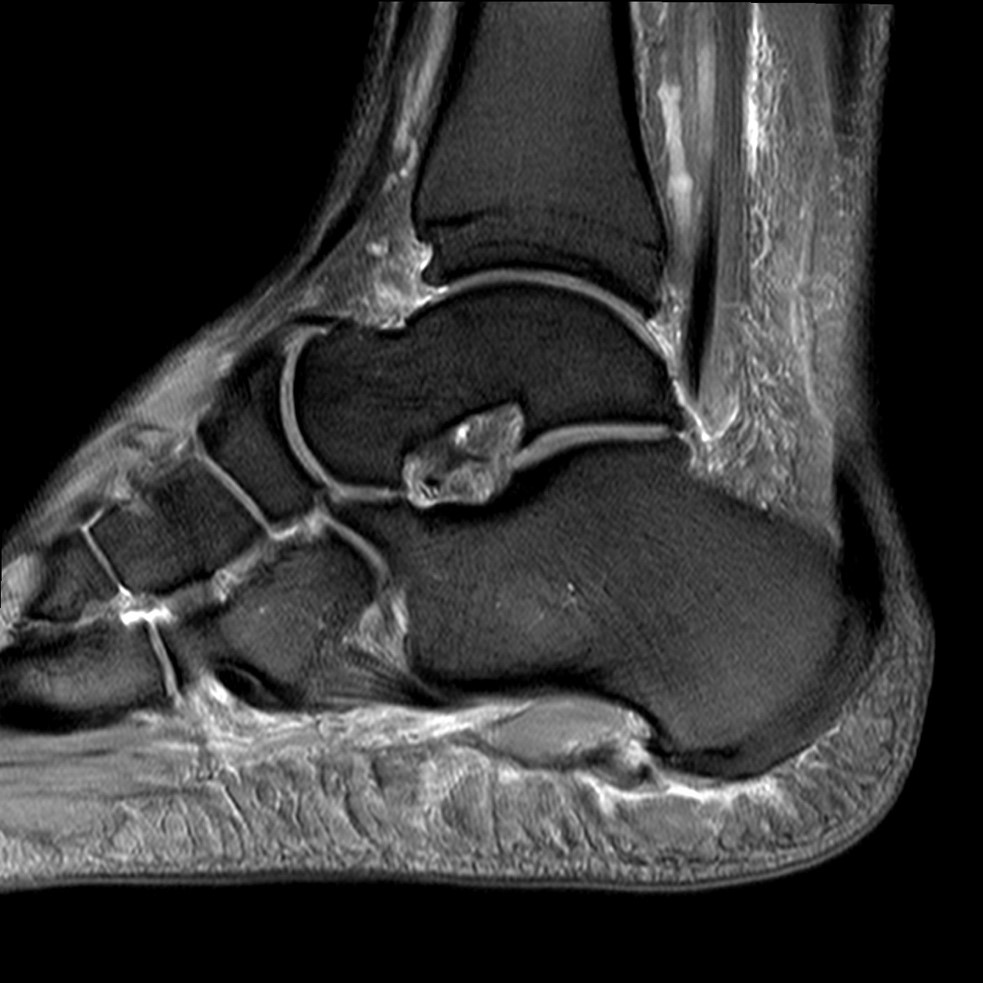

Abbildung 1: Plantarer und dorsaler Sporn im Röntgenbild und im MRT

Abb. 1a und Abb. 1b: großer dorsaler Fersensporn und ein minimaler plantarer Sporn, Patient, 50 Jahre.

Abb. 1c: Bild eines isolierten großen plantaren Fersensporns. Patientin, 32 Jahre.

Zum Lesen der Bildbeschreibung und zur Vollansicht bitte die Bilder anklicken. Bilder: Manfred Thomas.

2.3. MRT

Eine Kernspinuntersuchung erlaubt eine Feindiagnostik des Tarsaltunnels, bei hoher Auflösung können Sehnen, Nerv, Arterie und Venen sowie Veränderungen der Plantarfaszie selbst oder des Faszienursprungs mit Signalalterationen dargestellt werden. Aufgrund der Sensitivität des Verfahrens kann unterschieden werden, ob es sich um eine Veränderung des Ursprungs der Plantarfaszie oder um eine weiter distal gelegene Problematik handelt. Gelegentlich findet man auch Teilrupturen etwas distal des Ansatzes (siehe Abb. 2). Diese Methode erlaubt auch eine Aussage über knöcherne Veränderungen.

Abb. 2: Teilruptur Plantaraponeurose in der MRT Diagnostik

Eine Teilruptur der Plantaraponeurose kann ursprungsnah oder auch einige cm distal des Ursprungs als Folge einer direkten Gewalteinwirkung auftreten.

Zum Lesen der Bildbeschreibung und zur Vollansicht bitte das Bild anklicken. Bild: Manfred Thomas